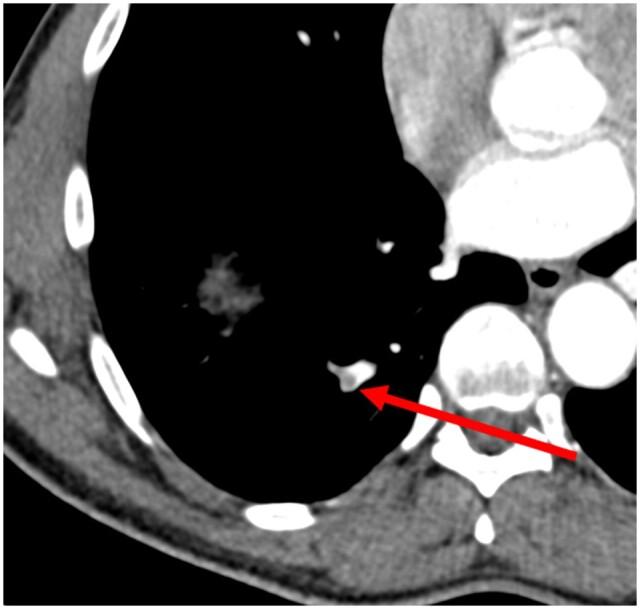

This diagnostic study assessed the accuracy of radiologists retrospectively, using the deep learning and natural language processing chest algorithms implemented in Clinical Review version 3.2 for: pneumothorax, rib fractures in digital chest X-ray radiographs (CXR); aortic aneurysm, pulmonary nodules, emphysema, and pulmonary embolism in CT images.

The missed findings were: 0.02% rib fractures, 0.51% aortic aneurysm, 0.32% pulmonary nodules, 0.92% emphysema, and 0.28% pulmonary embolism. The positive predictive values (PPVs) were: pneumothorax (0%), rib fractures (5.6%), aortic dilatation (43.2%), pulmonary emphysema (46.0%), pulmonary embolus (11.5%), and pulmonary nodules (9.2%). The PPV for pneumothorax was nil owing to lack of available studies that were analysed for outpatient activity.

The diagnostic accuracy of our radiologists generated missed findings of 0.02% for rib fractures CXR, 0.51% for aortic dilatation, 0.32% for pulmonary nodule, 0.92% for pulmonary emphysema, and 0.28% for pulmonary embolism for CT studies, all retrospectively evaluated with AI used as a quality tool to flag potential missed findings. It is important to account for prevalence of these chest conditions in clinical context and use appropriate clinical thresholds for decision-making, not relying solely on AI.